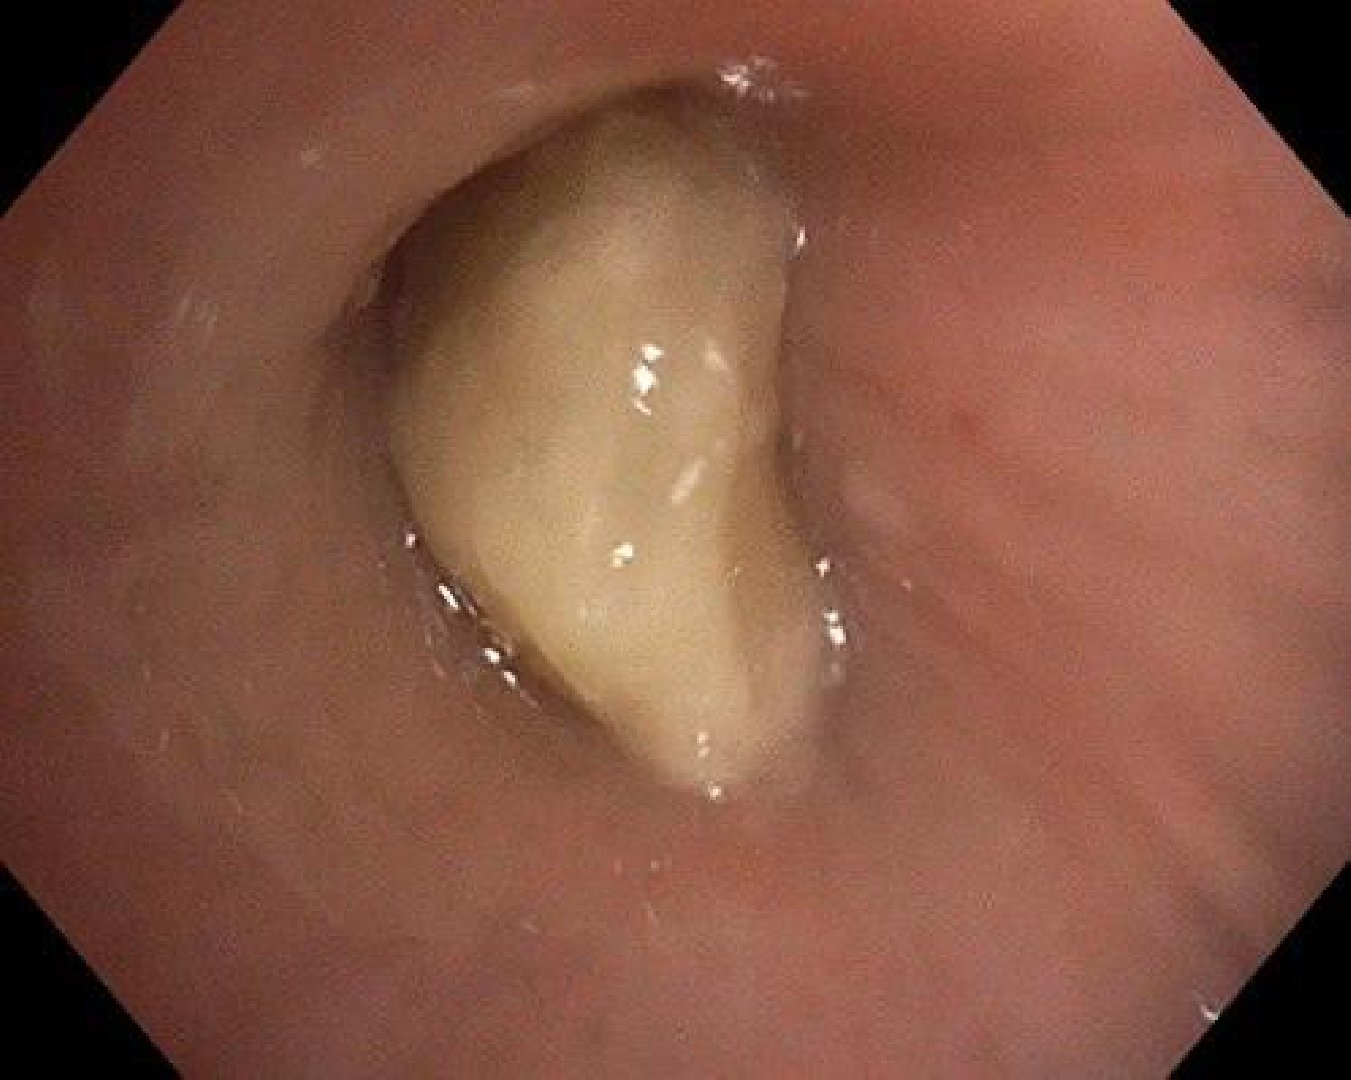

Малыш подавился во время еды. С высокой температурой и сильным кашлем его экстренно доставили в клинику в Красногорске. При проведении бронхоскопии врачи заметили инородное тело в дыхательных путях малыша. Оно вызвало нарастающее воспаление и грозило развитием пневмонии.

«Орех полностью перекрыл просвет промежуточного бронха. Такое состояние могло привести к дыхательной недостаточности и тяжёлому воспалению лёгкого. Учитывая риски, мы аккуратно извлекли инородное тело с помощью корзинки Дормиа и выполнили санацию дыхательных путей», – рассказал заведующий отделением эндоскопических методов диагностики и лечения Александр Иноземцев.